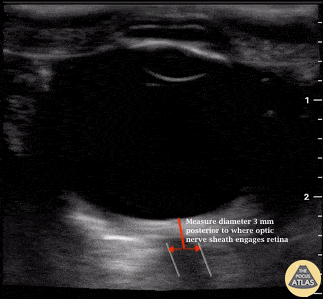

The optic nerves are encapsulated by a dural sheath arising from the meninges. Increases in intracranial pressure (ICP) are therefore transmitted to the CSF within the optic nerve sheath and result in dilation of the optic nerve sheath diameter.